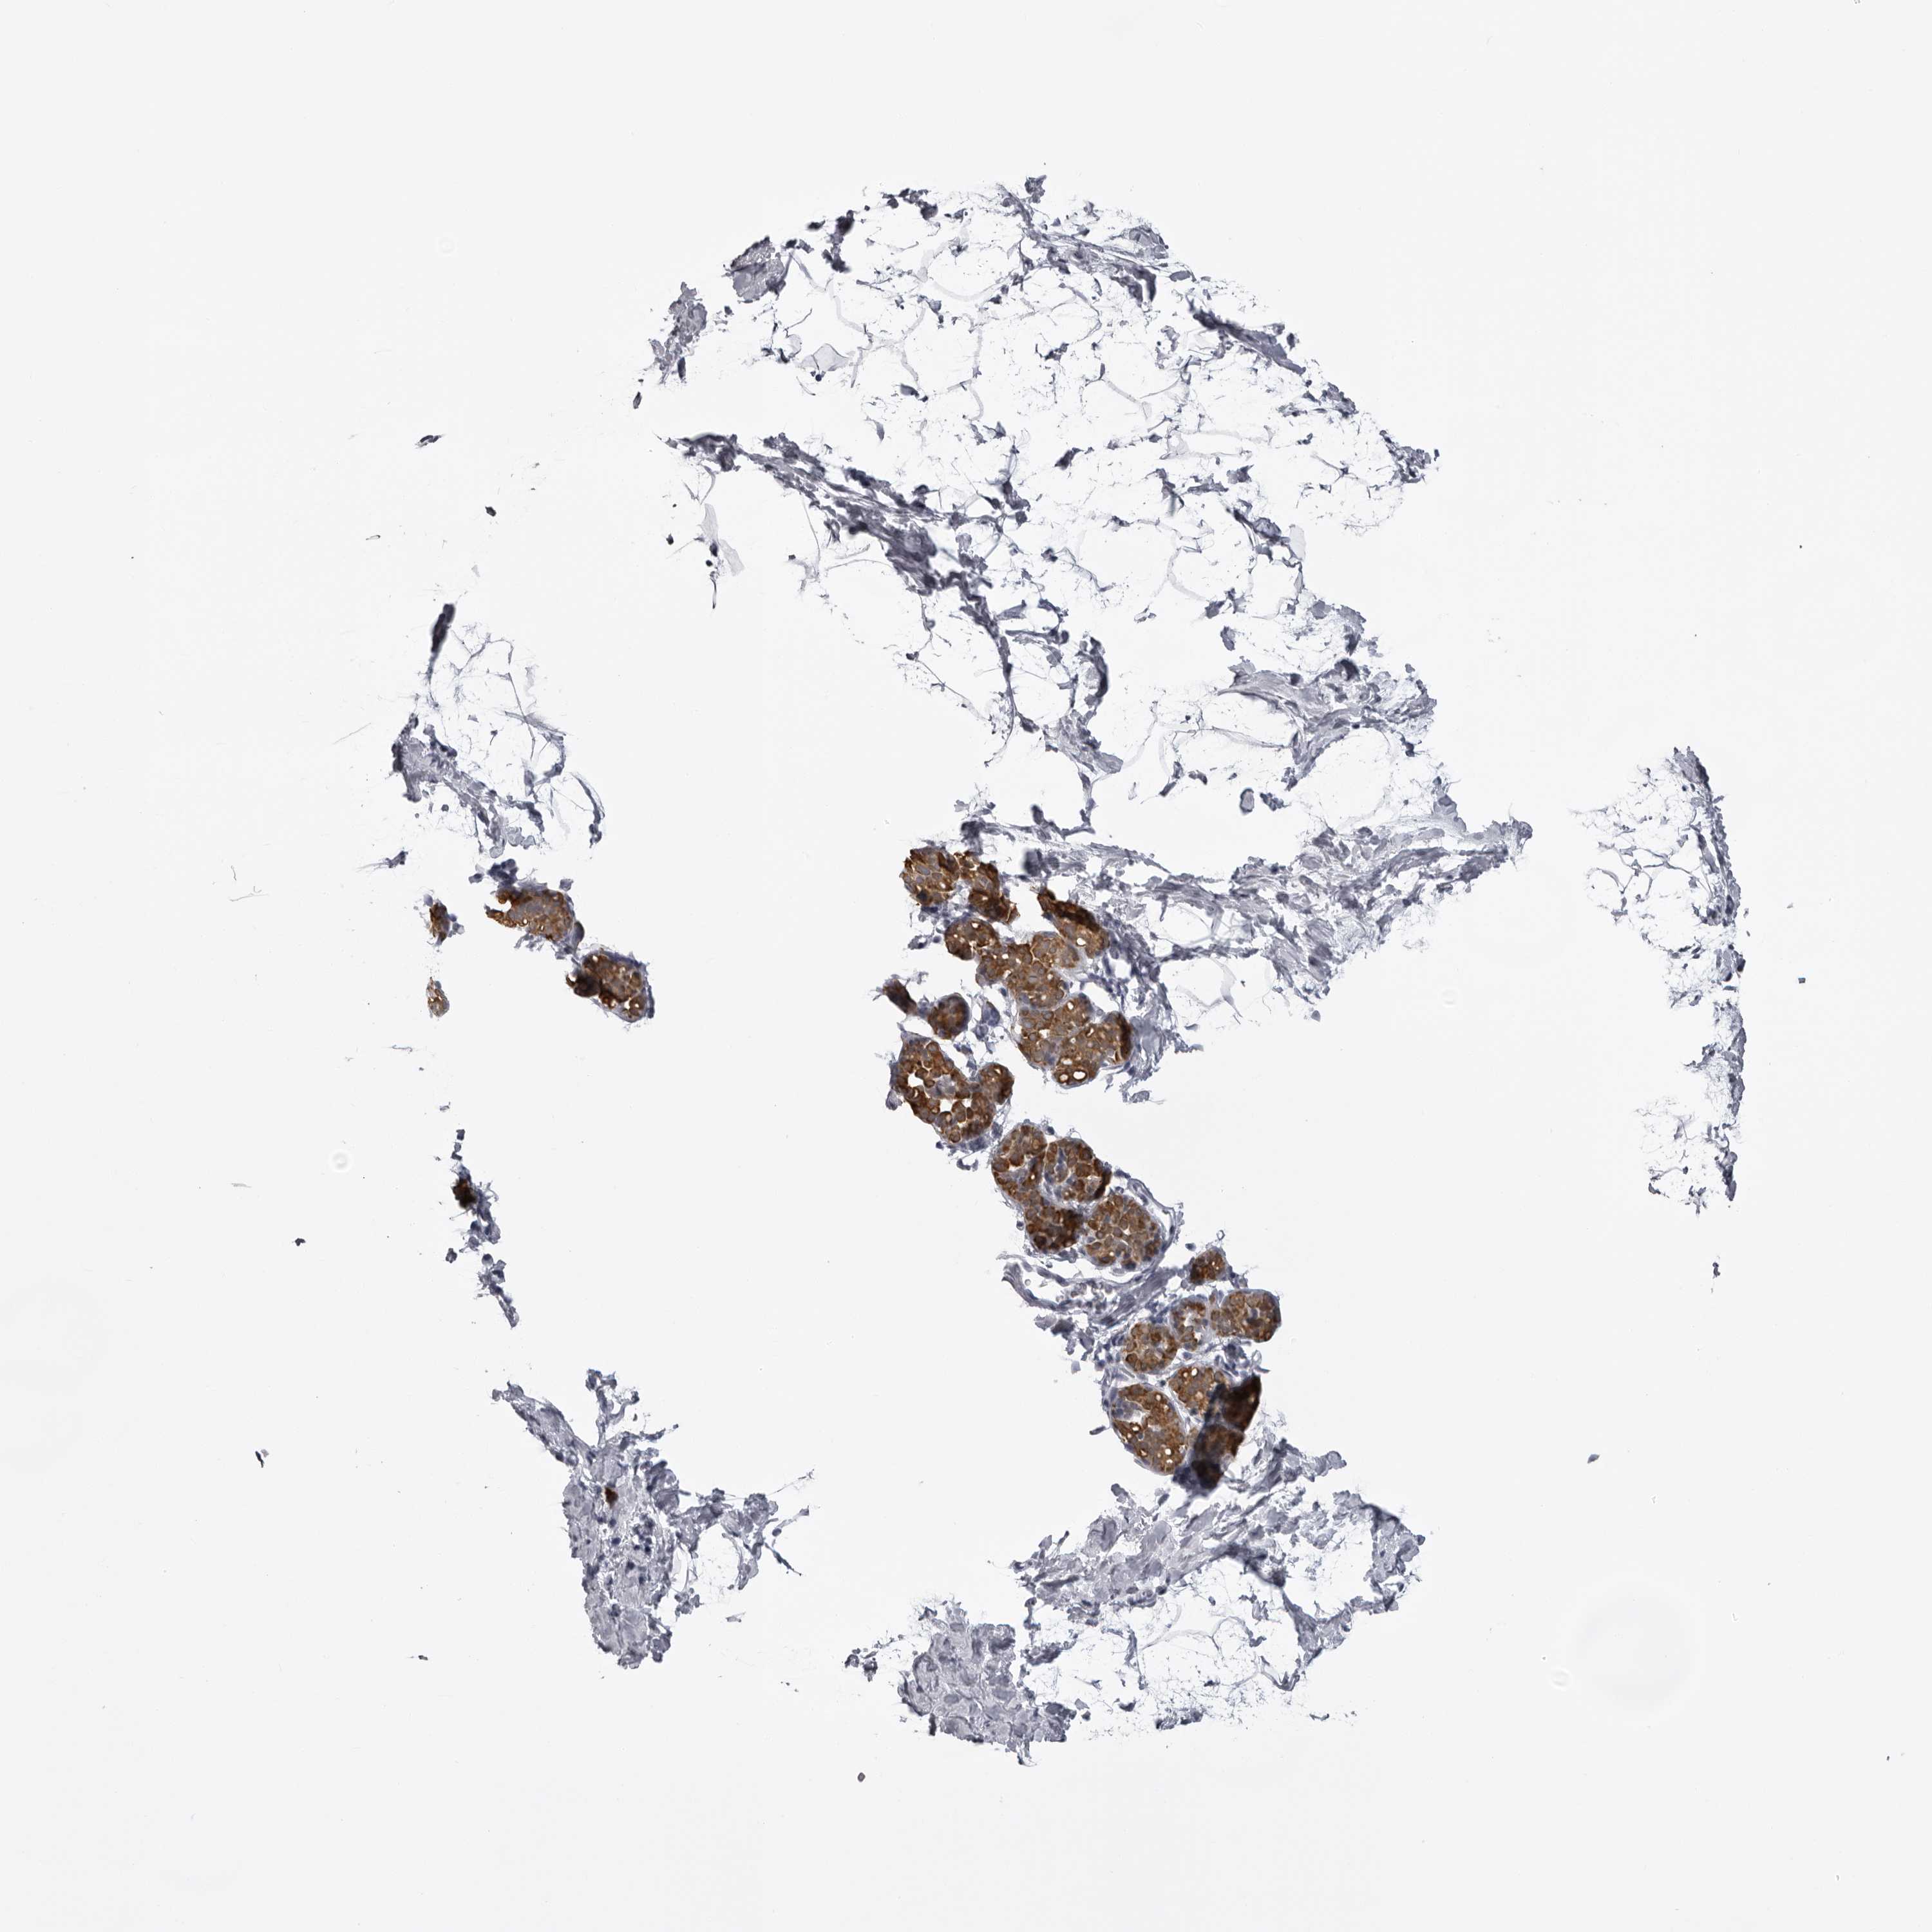

BREAST - Antibody stainingi

Antibody staining in the annotated cell types in the current human tissue is reported as not detected, low, medium, or high, based on conventional immunohistochemistry profiling in selected tissues. This score is based on the combination of the staining intensity and fraction of stained cells.

Each image is clickable and will lead to virtual microscopy that enables deeper exploration of all samples and also displays staining intensity scores, fraction scores and subcellular localization as well as patient and tissue information for each sample.

Antibody HPA027468Antibody HPA028668

Adipocytes LowNot detected

Glandular cells LowHigh

Myoepithelial cells LowNot detected